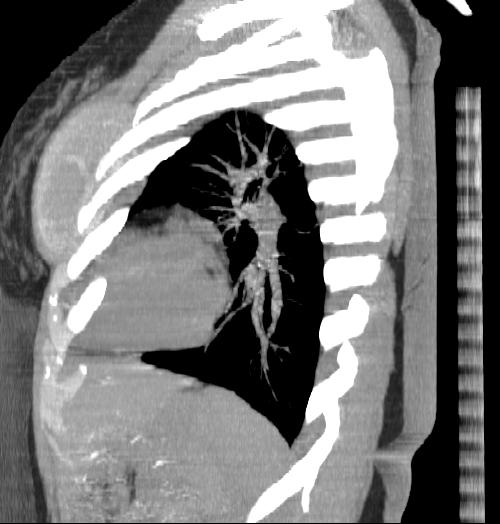

New CT images (without contrast) for 40 year old female with silicone breast implants. Formal diagnosis is expected soon. Images from 2010 can be seen here http://radiology-images.blogspot.com/p/40-year-old-female-silicone-implants.html